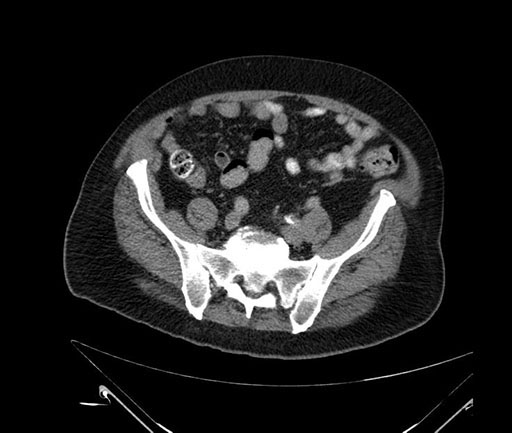

Whipple (pancreaticoduodenectomy) [case 7]

Axial - 3 months prior